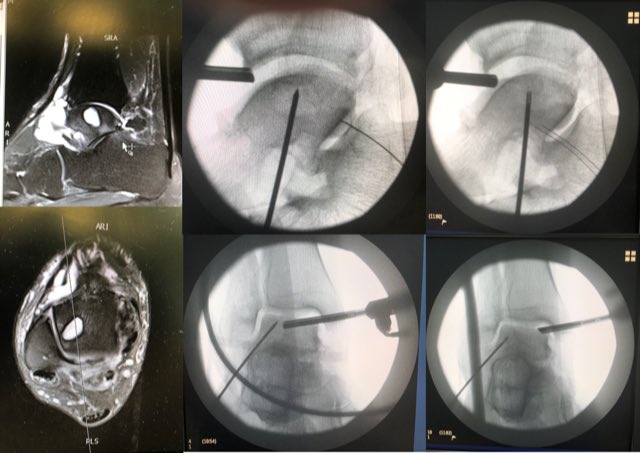

Interesting week; some great cases. (images with permission) This patient had minimally invasive repair of subchondral lesion arthroscopically. Good series of these now...